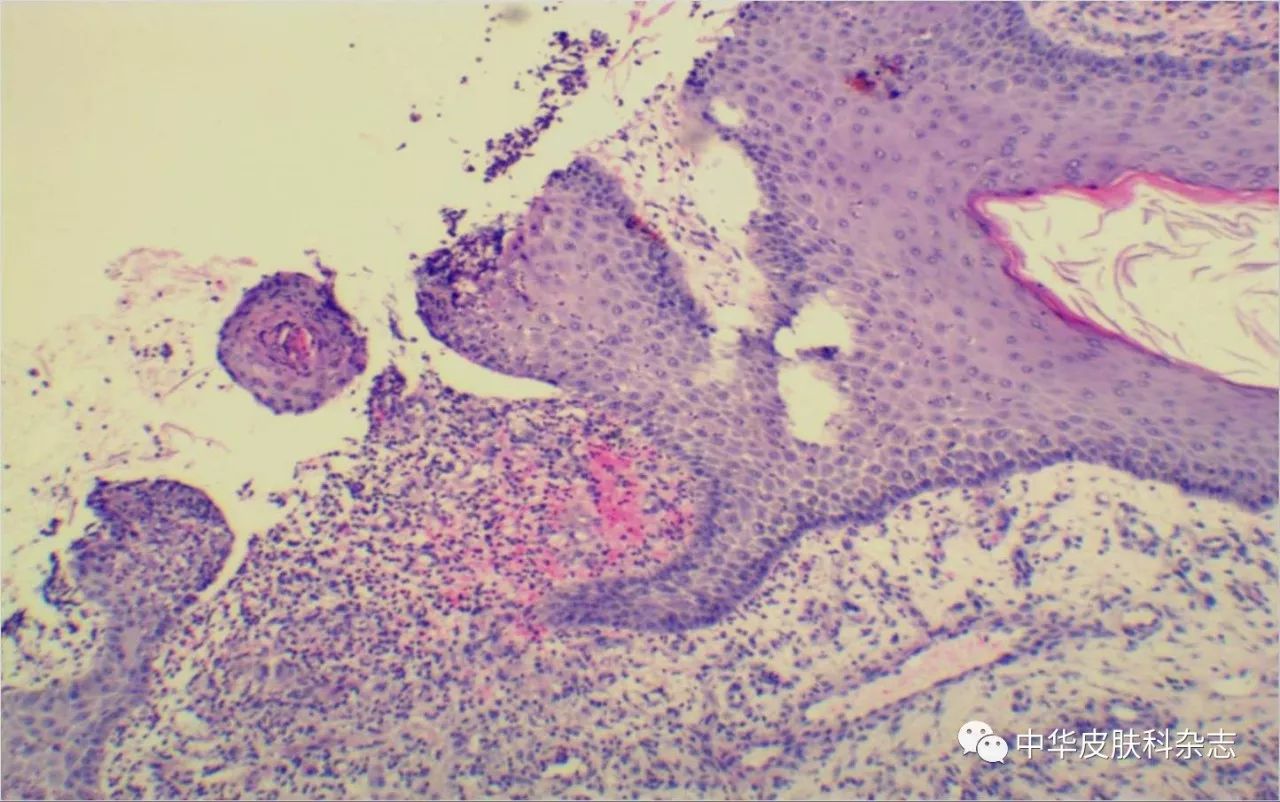

聚合性痤疮继发鳞状细胞癌并局部淋巴结转移1例

病例

2025-08-21